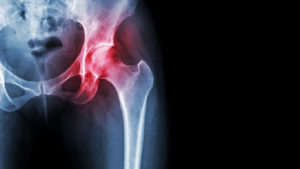

Finding the Best Orthopedic Surgeon for Your Hip Replacement

Among the 32.5 million Americans with osteoarthritis, around 8% have hip arthritis. While early stages of hip arthritis can be managed with conservative treatments, eventually, surgery may be necessary for more permanent relief. Thankfully, total hip replacement is one of the most successful total [Read More]